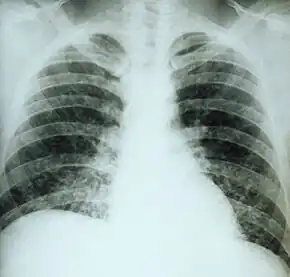

If symptoms of histoplasmosis infection occur, they start within 3 to 17 days after exposure; the typical time is 12–14 days. Most affected individuals have clinically silent manifestations and show no apparent ill effects. The acute phase of histoplasmosis is characterized by nonspecific respiratory symptoms, often cough or flu-like. Chest X-ray findings are normal in 40–70% of cases.[12] Chronic histoplasmosis cases can resemble tuberculosis;[13][14] disseminated histoplasmosis affects multiple organ systems and is fatal unless treated.[15]